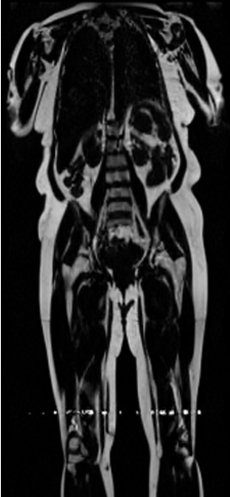

Preservation of Spine Curvature. For the spine segmentation on UK Biobank, we use a UNet++ model [81] with Dice Loss and use the curvature prediction of the spine followed in [9]). We measure the Pearson correlation factor [9] of spine curvature measured on the generated MRIs where the input is a single MRI coronal slice, or a single sagittal slice against the curvature of reference real MRIs of the same samples. The correlation coefficients are 0.89 for the coronal MRIs and 0.88 for the sagittal MRIs on the test set of 308 human-annotated angles.

B.3 Preservation of Spine Curvature and Fat

For the spine segmentation on UK Biobank, we use a UNet++ model [81] with Dice Loss. We use a model trained to predict curves on DXA on UK Biobank [9]. We show in Figure 20 that generated MRIs preserve the spine curvature from normal to severe scoliosis cases. We also study the case when DXA is used to generate the MRIs and show in Figure 14 how the correlation to real curvatures compares to the input MRI case. The curvatures of the MRI generated from the coronal plane match the DXA curvatures more than the curvatures generated from sagittal MRI. This is expected since the antero-posterior plane of DXA is equivalent to the coronal plane for MRIs. This also explains the greater Pearson’s correlation coefficient of the coronal MRI (0.89) and DXA-generated curvature (0.88) compared to sagittal-generated curvature (0.87) relative to the reference curvature on the coronal plane. We observe though that MRI generation using X-Diffusion from another plane than the conventional plane for scoliosis assessment is valid.

D.4 Spine Curvature Analysis

For the spine segmentation on UK Biobank, we use a UNet++ model [81] with Dice Loss. We use a model trained to predict curves on DXA on UK Biobank [9]). We measure the Pearson correlation factor [9] of spine curvature measured on the generated MRIs where the input is a single MRI coronal slice, a single sagittal slice, or from the paired DXA, against the curvature of reference real MRIs of the same samples. The correlation coefficients are 0.89 for the coronal MRIs, 0.88 for the sagittal MRIs, and 0.87 for the DXAs on the test set of 308 human-annotated angles. We can then bin the curvature, , of the spines under different scoliosis categories based on human-annotated angles: mild: , moderate: , and severe . We show the results in Figure 20. This illustrates that the generated MRIs preserve the spine curvature from normal to severe scoliosis cases.